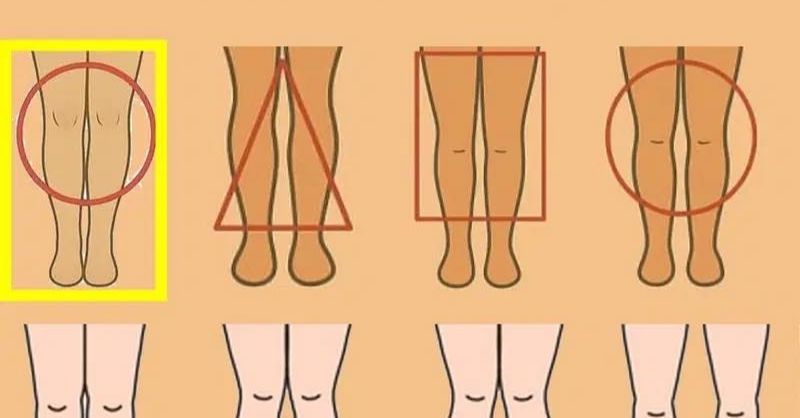

What can your legs reveal about your health?

Ever noticed something unusual about your legs—swelling, tingling, or a change in shape—and wondered what it really means? Your legs can reveal surprising insights about your overall health....